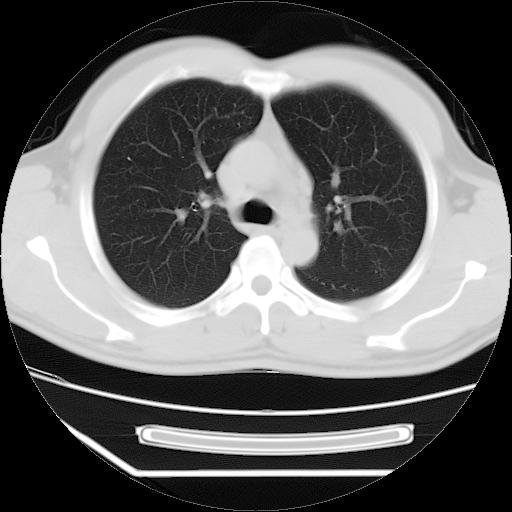

男,38岁,于2009年8月9日晚突发左侧胸痛,今x线提示左下肺阴影,为了明显确诊断,行ct检查,

血常规:嗜酸性细胞增高,单核细胞增高。

病灶发生在下叶,密度均匀,边缘模糊、毛糙,周围血管纹理增强扭曲改变,靠近胸膜处病灶胸膜反应明显。

支持考虑---球形肺炎。

左肺舌叶病变。主体病灶呈类圆形中心密度低,成液化趋势周边班片影分布

考虑肺脓肿

虽然实验室检查支持炎性病变,且病变内有坏死改变(中央呈大片状低密度影),但仍不能掉以轻心,鳞癌也可以有这种影像改变。